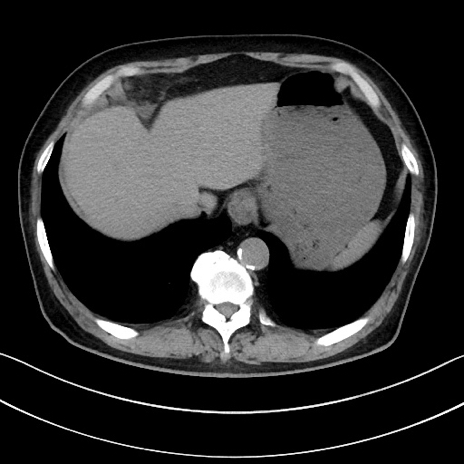

冠状断像

【症例】70歳代男性

【主訴】腹痛

【現病歴】今朝から腹痛あり。全体的に痛い。特に左上の方。排ガスが今日はない。冷や汗が出る。

【既往歴】直腸癌術後

【身体所見】左側腹部〜上腹部に圧痛あり。腹膜刺激症状明らかなではない。軽度反跳痛。左下腹部に術後瘢痕あり。

【データ】WBC 7700、CRP 0.02